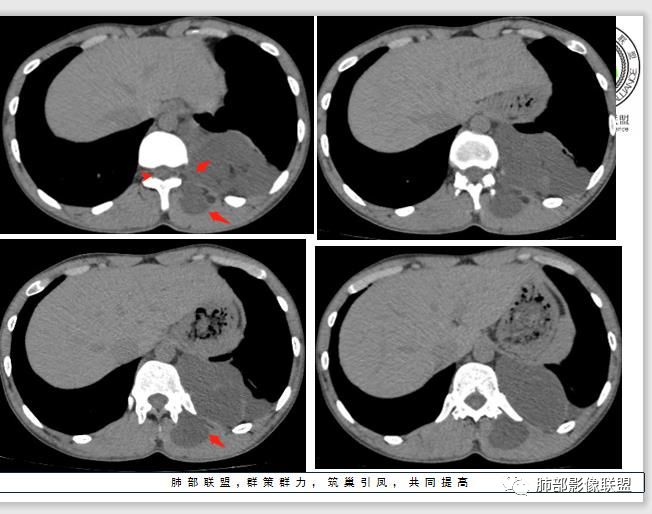

现在我们重新回顾性分析这个病例的影像特点:

1.含有少量脂肪密度成分,位于病灶中央区,应当是病灶内的一部分,或者说至少这部分不是被包绕卷入的。常见病灶内含有脂肪组织的肿瘤:多种脂肪瘤、脂肪肉瘤、畸胎瘤、其他肿瘤伴脂肪化生或分化。

2.病灶中间弧形稍高密度影,提示纤维组织可能,而且很有张力并呈分叶状,伴弧形钙化,提示这个倾向于病灶的包膜。

我们知道囊性成熟畸胎瘤中外胚层来源的上皮组织有腺体,有脂质,分泌粘液,囊性病灶有张力,囊壁也可以有弧形钙化,但易脂质上浮呈液平面,囊性畸胎瘤较少见如此明显的分叶,更少见在不同组织区间漫延串扰。

3.部位深在且四处侵入,含脂质较少或整体密度高于脂肪的脂肪类肿瘤应当想到脂肪肉瘤的可能性,因为它可以粘液样变。

但本例病灶边界清楚,有一定规模而相邻骨质未见异常,提示整体倾向良性或者恶性程度不高。

包膜钙化往往提示病灶存在时间较长且较为固定。

良性脂肪肿瘤有多种,脂肪瘤、纤维脂肪瘤、血管脂肪瘤、神经脂肪瘤、梭形细胞脂肪瘤、冬眠瘤等等……

4.冬眠瘤为含有棕色脂肪成分的脂肪瘤,又称为棕色脂肪瘤,因类似冬眠动物的冬眠腺而得名。良性,生长缓慢,好发年龄30-40岁,男性稍多。血管丰富有时会触及局部皮温相对高。

脂肪瘤临床触诊偏柔软较有特点,CT影像脂肪组织成分是最重要的依据之一。

本例无论是临床还是影像都可能怀疑到脂肪类肿瘤,但落实到冬眠瘤难度颇大。